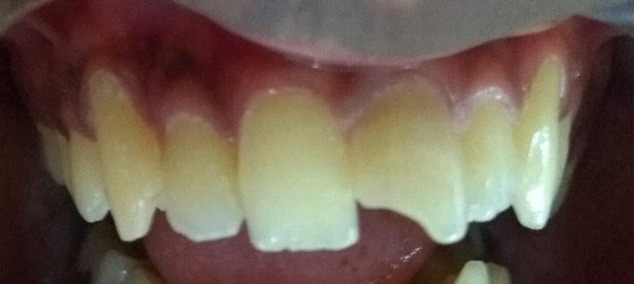

PRE - OP POST - OP